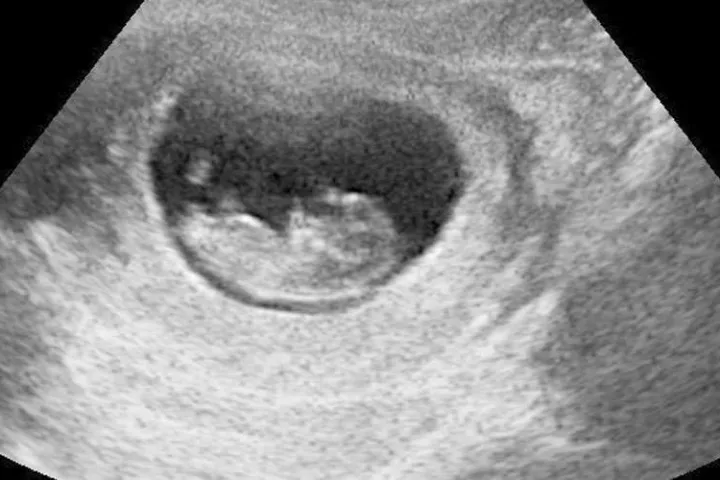

Uma ultrassonografia. Foto Wikipédia (Domínio público)